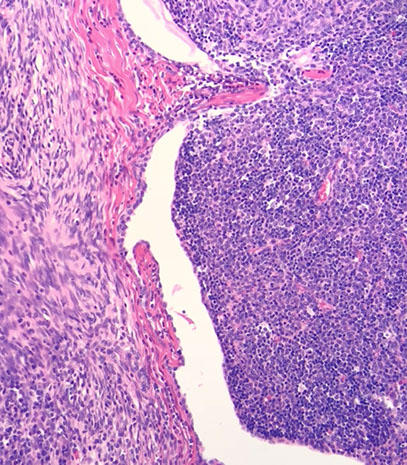

Histologically subclassified as A, AB, or B1-B3, based on "organotypical" features (i.e. histologic resemblance to normal thymic development)

- Mixed patterns may occur within the same tumor, necessitating the need for adequate sampling

-- Recommended to classify thymomas with heterogenous patterns by the predominant pattern, followed by the minor components in 10% increments

Type A and AB is more spindly cells

-- most type AB have focal immature lymphocytes (thymocytes, type-B like) and focal lymph poor areas (type A-like)

- B1-B3 more epithelioid

-- B1 has more lymphs and less epithelioid cells, B3 has less lymph and more epithelioid cells

- B2 intermediate, with some epithelial cell clusters

-- medullary islands essentially req'd to dx type B1

IHC: thymocytes (immature lymphs) + for CD99, CD1a and TdT; epithelial cells CK / p63+

- negative CD5 and CD117 (vs thymic carcinoma)

DDx: T-LBL, thymic hyperplasia, thymic carcinoma

Thymoma

Thymoma AB

thymoma type B1

B3 thymoma